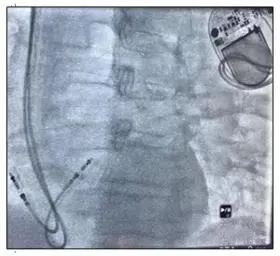

在积水潭医院介入中心护士、起搏器技师、监护室医师、心内科医师的共同合作下,患者在局麻下实施了MICRA无导线起搏器植入术。术中,刘巍主任团队通过股静脉穿刺顺利将起搏器导管送到心腔内部,经过X线图像确定了起搏器释放位置。尽管患者肥胖体型和心腔结构变化给植入部位定位带来了较大困难,但刘巍主任团队通过多体位、右心室内充分造影指示,成功将无导线起搏器固定于右心腔内。整个手术过程仅用30分钟,随后的起搏器调试也提示起搏器工作良好。